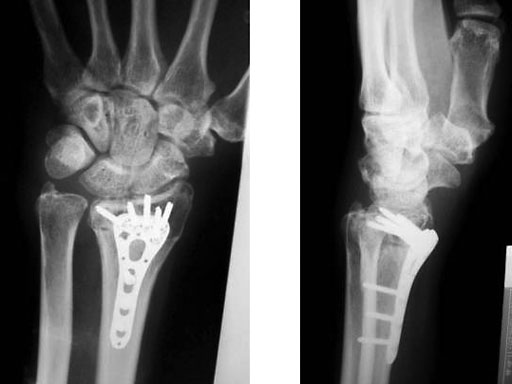

Age 63, male, motorcycle accident

Fig 3a-b Post-op 3 months